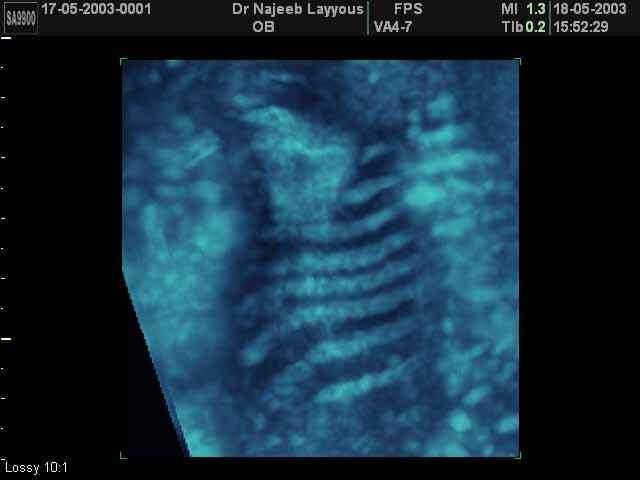

- Fetal Skeleton Ultrasound Photos